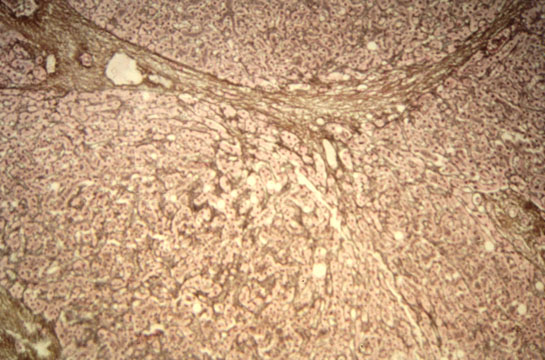

Confluent necrosis

Fig 46 - CONFLUENT NECROSIS: This necrosis is not spotty but involves masses of cells distributedi a certain region of the lobule and therefore it is:

1-ZONAL when it affects one of the 3 zones of the lobule:

centrolobular, perilobular, midlobular.

2-BRIDGING when it occurs between the portal fields and central veins: porto-portal, porto-central, central-central.